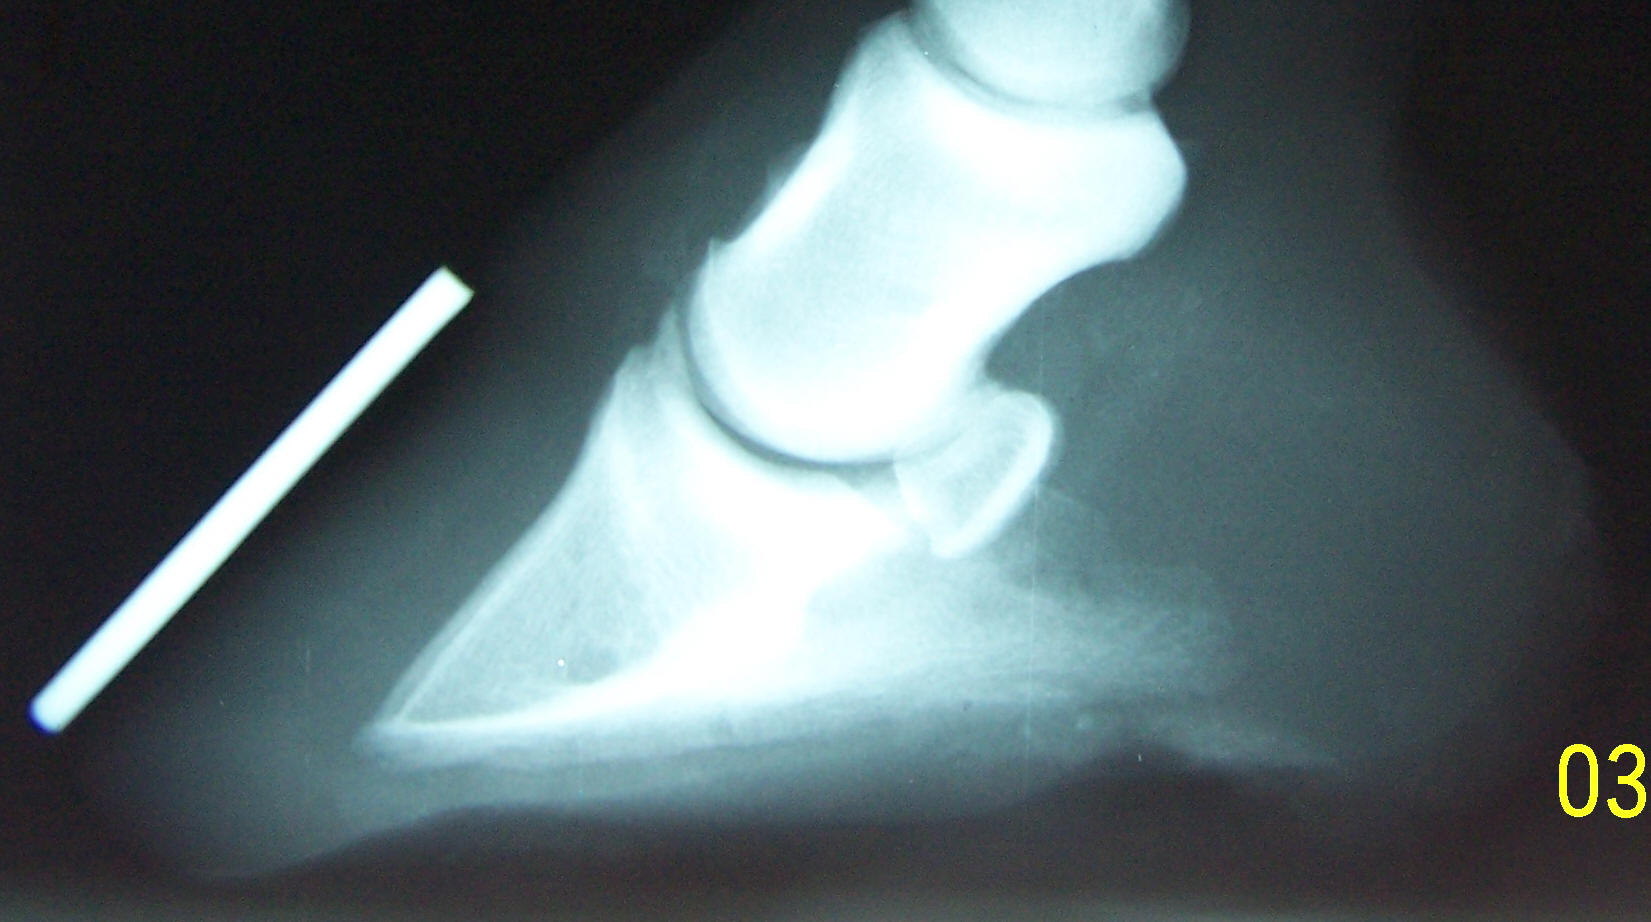

the shape of the soles and particularly, the height of the

collateral grooves from the ground. The wild hoof below has a

wire placed in the bottom of the collateral groove to help you

visualize this on the radiograph.